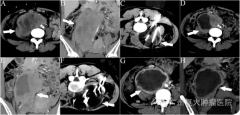

论文作者单位是中山大学一附院和暨南大学广州复大肿瘤医院。文章回顾分析两家医院72例...